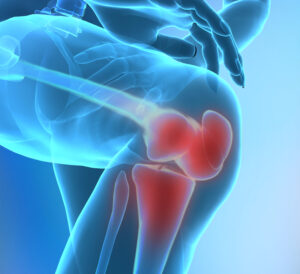

Kalça Eklemi Ağrısı

Kalça eklemi, vücudumuzun en önemli eklemlerinden biri olup, hareket kabiliyetimizi büyük ölçüde etkiler. Yürüme, koşma, merdiven çıkma gibi günlük aktivitelerde …